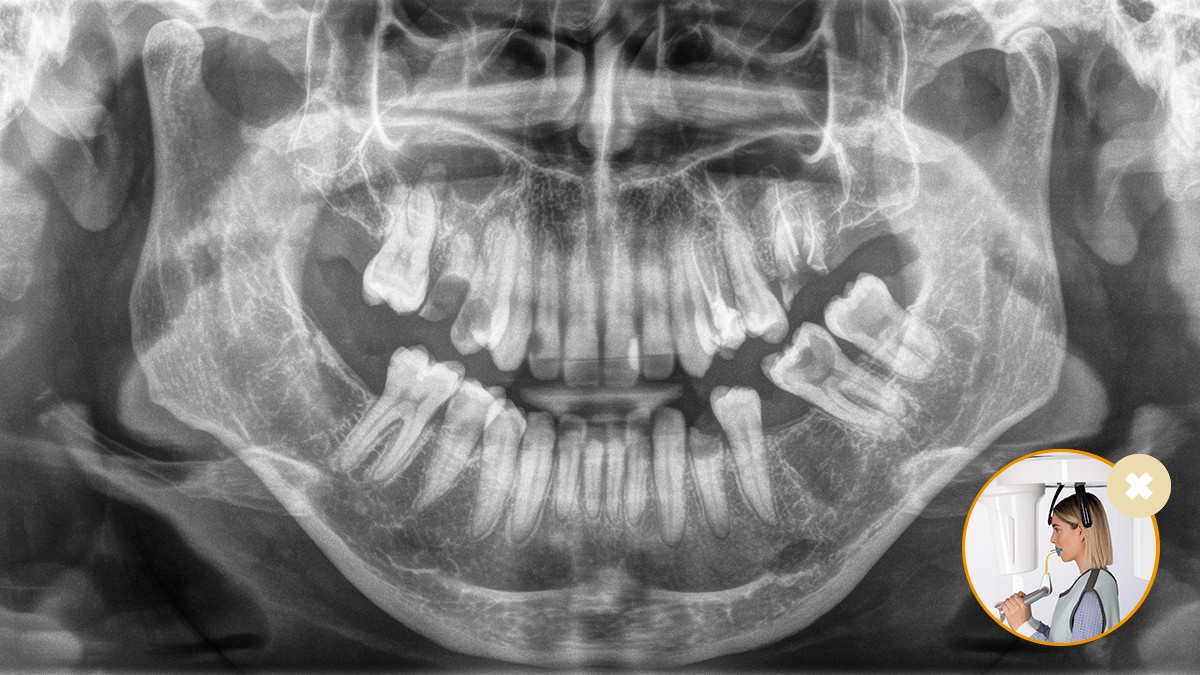

Un positionnement correct du patient mène à une qualité d’image élevée, essentielle pour un diagnostic fiable et améliore l’expérience du patient.

Voici notre concept à 10 points pour un positionnement facile du patient et une imagerie radiographique efficace. Il repose avant tout sur deux principes : une qualité d’image supérieure et le confort du patient et de l’assistant.

Le fonctionnement du bloc de morsure occlusale ne pourrait pas être plus simple. Avec l’aide des symboles et des couleurs affichés sur l’écran de l’appareil à rayons X, les praticiens disposent de toute l’information nécessaire pour un réglage fin optimal de l’appareil. Les flèches lumineuses indiquent la direction dans laquelle l’unité doit être déplacée pour obtenir une inclinaison idéale de la tête. L’appareil s’arrête automatiquement une fois que la position correcte est atteinte.